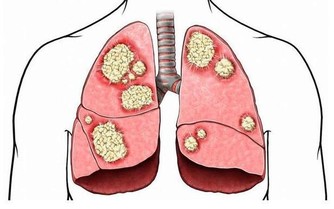

現代研究發現:蒲公英具有廣譜殺菌和抑菌作用,有“天然抗菌素”之美譽,在一定程度上可代替抗菌素,對臨床常見感染菌,尤其是革蘭陽性、陰性球菌有較好的抑菌活性。用於上呼吸道感染,急性支氣管炎咽喉炎、急性扁桃體炎、乳腺炎、乳腺增生、尿路感染、胃炎、肝炎、膽囊炎、感冒發熱等症。